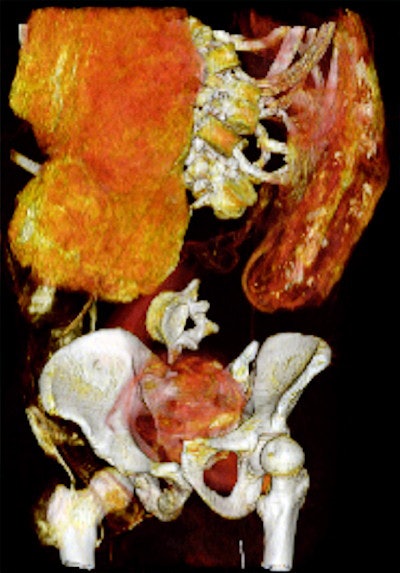

Dr. Sahar Saleem, a professor of radiology at Cairo University who specializes in CT mummy imaging, and archeologist Zahi Hawass, PhD, have used CT scans and 3D reconstructions to suggest he had multiple killers. They have presented their findings in an article published on 17 February in Frontiers of Medicine that received over 10,500 page views by 21 February.

CT revealed details of the head injuries, including wounds that had not been discovered in previous examinations and had been skillfully hidden by the embalmers. The mummy's deformed hands indicate that Seqenenre may have been captured on the battlefield, and his hands were tied behind his back, preventing him from deflecting the fierce attack on his head.

The CT scans, combined with other evidence, suggest the execution was carried out by multiple attackers, which the scientists confirmed by studying five different Hyksos weapons that matched the king's wounds. The study also determined that Seqenenre was about 40 when he died, based on the detailed morphology revealed in the images, providing the most precise estimate to date, according to the authors.